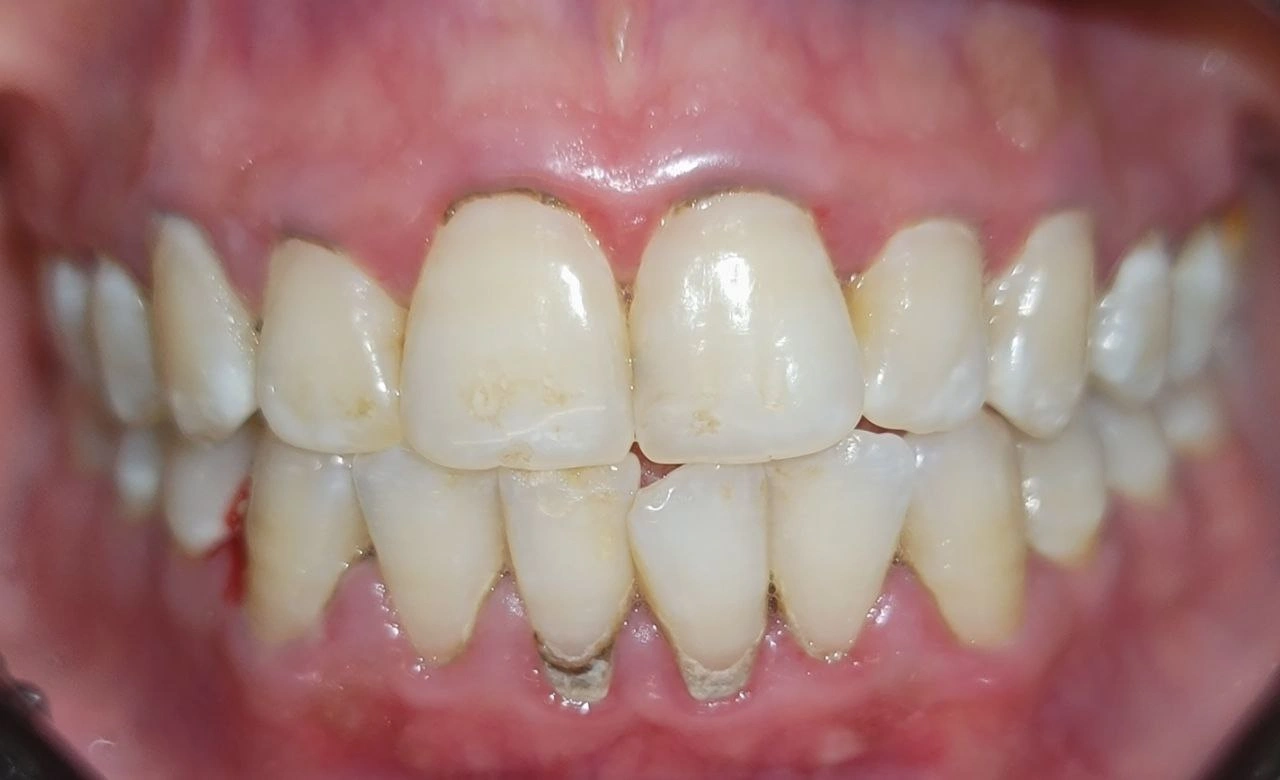

Clinical Cases